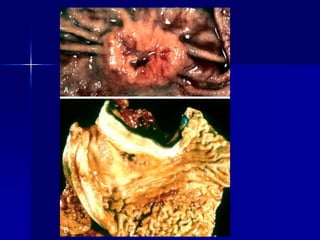

Una mujer de 74 años con sangre oculta

en las heces tiene un nivel de hematocrito

de 35,7% (nl 35% a 46%), un MCV de 79

fL [fL=fentolitro=10-15 L] (nl 78 a 102 fL),

y recuentos de plaquetas y glóbulos

blancos normal . Se muestran los

hallazgos pertinentes en la colonoscopia.

1. ¿Cuáles son los dos diagnósticos que

puedes hacer?

2. Explique los hallazgos de laboratorio.